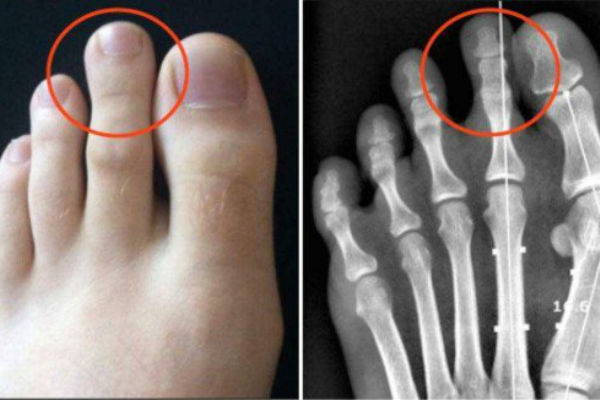

Zašto je kod nekih ljudi drugi nožni prst duži od...

Grčko stopalo! – JESTE LI MEĐU 14%...